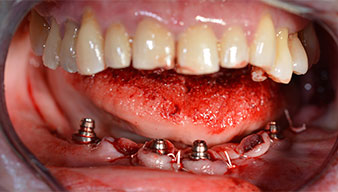

A three-dimensional cone beam computed tomography scan (CBCT, Planmeca) was performed to aid planning and minimize risks. This revealed that the quality and quantity of the available bone were sufficient for the surgery and immediate restoration using the Fast & Fixed method. Following the protocol for this concept, the implants are inserted at 35, 32, 42 and 45. Angling the distal implants by up to 45° shifts the emergence profile to posterior and generates a larger support polygon (Fig. 3).

After removal of the residual dentition in the mandible, the alveolar crest was exposed from 37 to 47.

The mental foramen was first identified as a limiting anatomical structure and then the cortical bone of the crest was smoothed with the straight handpiece and a large rose-head bur (Fig. 4).

Angled abutments (35°) were screwed in to compensate for the divergence of the distal implants, with the result that the emergence profile of all implants was as perpendicular as possible to the bite plane. This is a prerequisite for occlusal placement of the provisional and subsequently the permanent denture (Fig. 15 and 16).